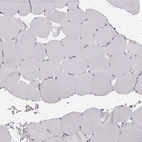

Immunohistochemistry analysis in human parathyroid gland and skeletal muscle tissues using HPA039686 antibody. Corresponding CASR RNA-seq data are presented for the same tissues.